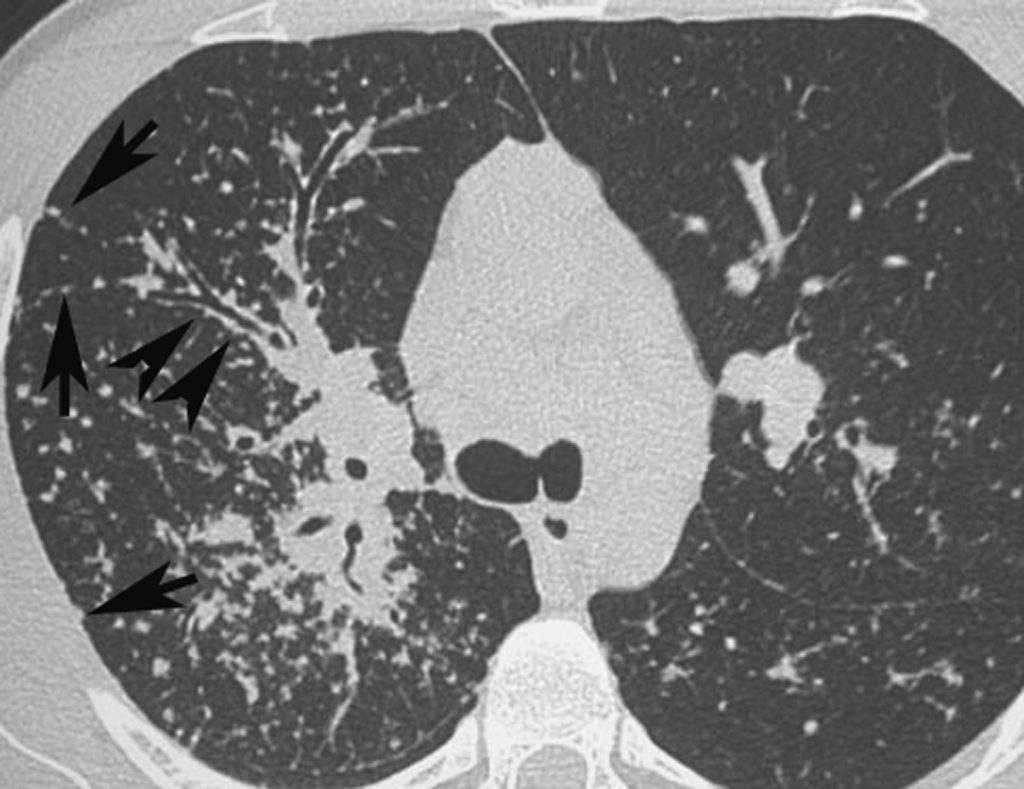

Fig. 97.4. Sarcoïdose.

Présence de micronodules dans la région moyenne des poumons, situés en région sous-pleurale, le long des septa interlobulaires (flèches) et le long des bronches (têtes de flèches).

Source : CERF, CNEBMN, 2022.